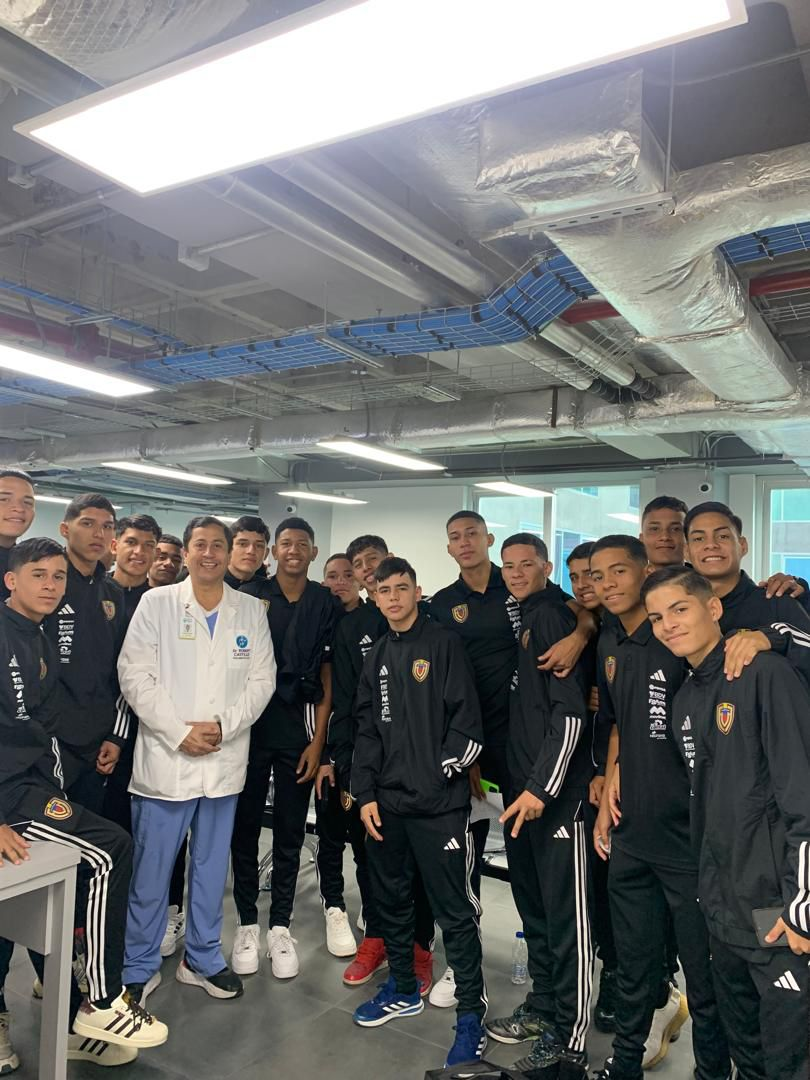

Con más de 27 años de experiencia en traumatología y ortopedia, he entendido que detrás de cada radiografía o diagnóstico hay una persona con el deseo profundo de recuperar su libertad. En el Consultorio 66, mi enfoque combina el rigor científico de vanguardia con una mística de servicio profundamente humana.

Soy el Dr. Robert Castillo, y mi misión es que recuperes la libertad de moverte. Sé que detrás de cada consulta hay una meta detenida: volver a entrenar, trabajar sin limitaciones o simplemente disfrutar de tu familia sin dolor.

"No solo sanamos, optimizamos tu retorno al campo."

"Cuidamos hoy la estructura del adulto de mañana."

Atención 360° para el atleta: desde el diagnóstico preciso hasta la rehabilitación personalizada. Mi reciente especialización en la Universidad de los Andes (2024) avala un plan de retorno seguro y eficaz a la alta competencia.

"Bajo la dirección del Dr. Robert Castillo, nuestro equipo multidisciplinario trabaja en perfecta sincronía para transformar la precisión quirúrgica en una recuperación acelerada. Desde la alta especialización en cada articulación hasta el soporte técnico y humano en quirófano, nuestro compromiso es uno solo: devolverte la libertad de movimiento en el menor tiempo posible, porque entendemos que tu vida no puede esperar."

Entendemos que dar el primer paso hacia una recuperación puede generar dudas. En el Consultorio 66, no solo agendamos citas, abrimos las puertas a una nueva etapa de tu vida. Ya seas un atleta buscando volver al campo, un padre preocupado por su hijo o alguien que simplemente desea caminar sin dolor, estamos aquí para escucharte.